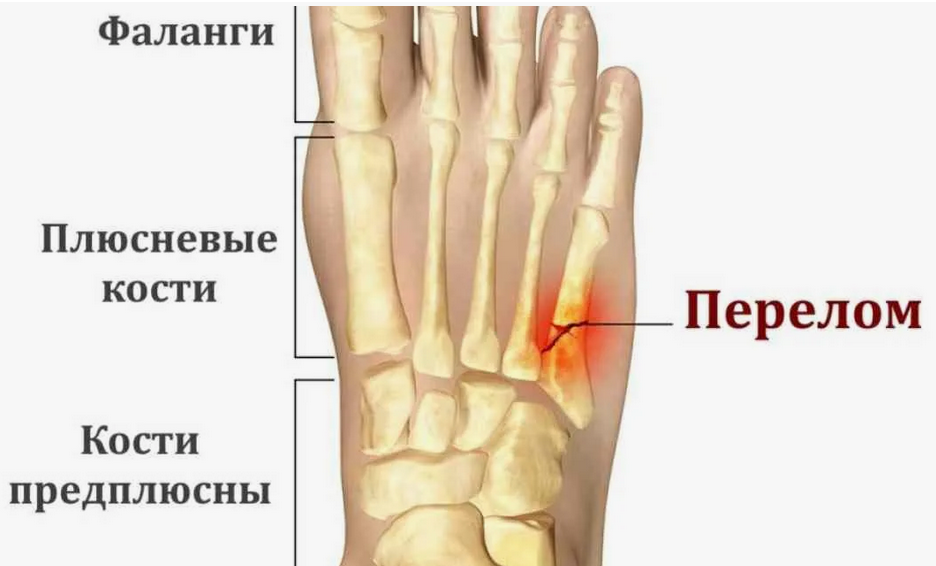

В случае перелома шейки бедра компания МосРентген Центр госпитализирует в Склиф для эндопротезирования.